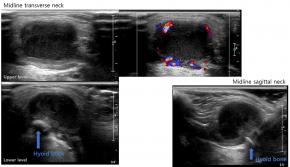

• Complicated cystic lesion in midline neck at the level of hyoid bone with internal debris, surrounding inflammatory change, and increased vascularity on Doppler study, suggestive of complicated thyroglossal duct cyst (TGDC).